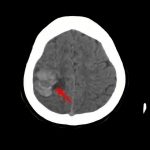

病名

断層撮影

手術前1